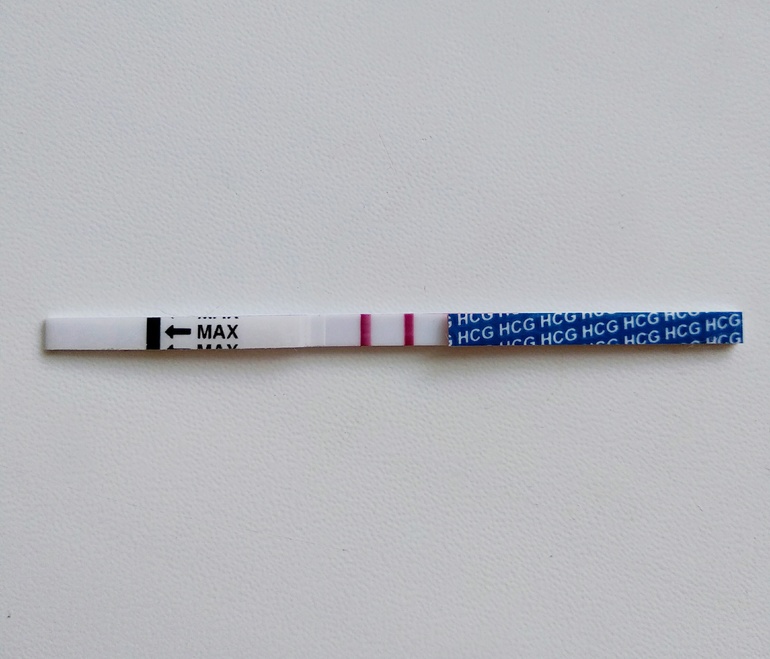

И традиционный красавчик-тест на 14 ДПП 🤗